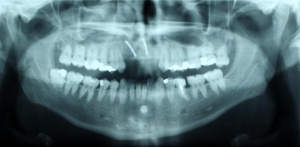

Die Planung erfolgt zunächst über eine 2D-Röntgenaufnahme (Panoramaschichtaufnahme) sowie über Modelle des Gebisses. Bei komplexen Rekonstruktionen des stomatognathen Systems kommen dreidimensionale Aufnahmetechniken (CT oder DVT) zur Anwendung, da dadurch eine genaue Darstellung des Knochenangebotes ohne Dimensionsverlust überlagerungsfrei möglich ist [Zöller 2007]. Präoperativ ist durch diese Unterlagen anschließend eine virtuelle Planung der Implantation mit geeigneten Computerprogrammen möglich, die im Anschluss beispielsweise durch individuell hergestellte Bohrschablonen intraoperativ umgesetzt werden kann.

Nach achtwöchiger Ausheilzeit wurde im Mai 2012 eine 3D-Planung der Implantation bei unklarem Knochenangebot durchgeführt. Hierzu erfolgte bei Zahnlosigkeit zur Verankerung der Planungsschablonen im Juni 2012 die Insertion von drei Miniimplantaten im Oberkiefer und drei Miniimplantaten im Unterkiefer. Zur besseren Stabilisierung der schon vorhandenen Totalprothesen wurden Druckknöpfe in die Prothesen eingebracht. Nach Herstellung der Planungsschablonen wurde Ende Juni 2012 eine Denta-CT durchgeführt.

Im Oberkiefer konnten mit der Planungssoftware SkyPlanX der Firma Bredent 6 Implantate mit BoneSplit geplant werden (Abb. 2), im Unterkiefer war eine Implantation aufgrund ungenügenden Knochenangebots nicht möglich.